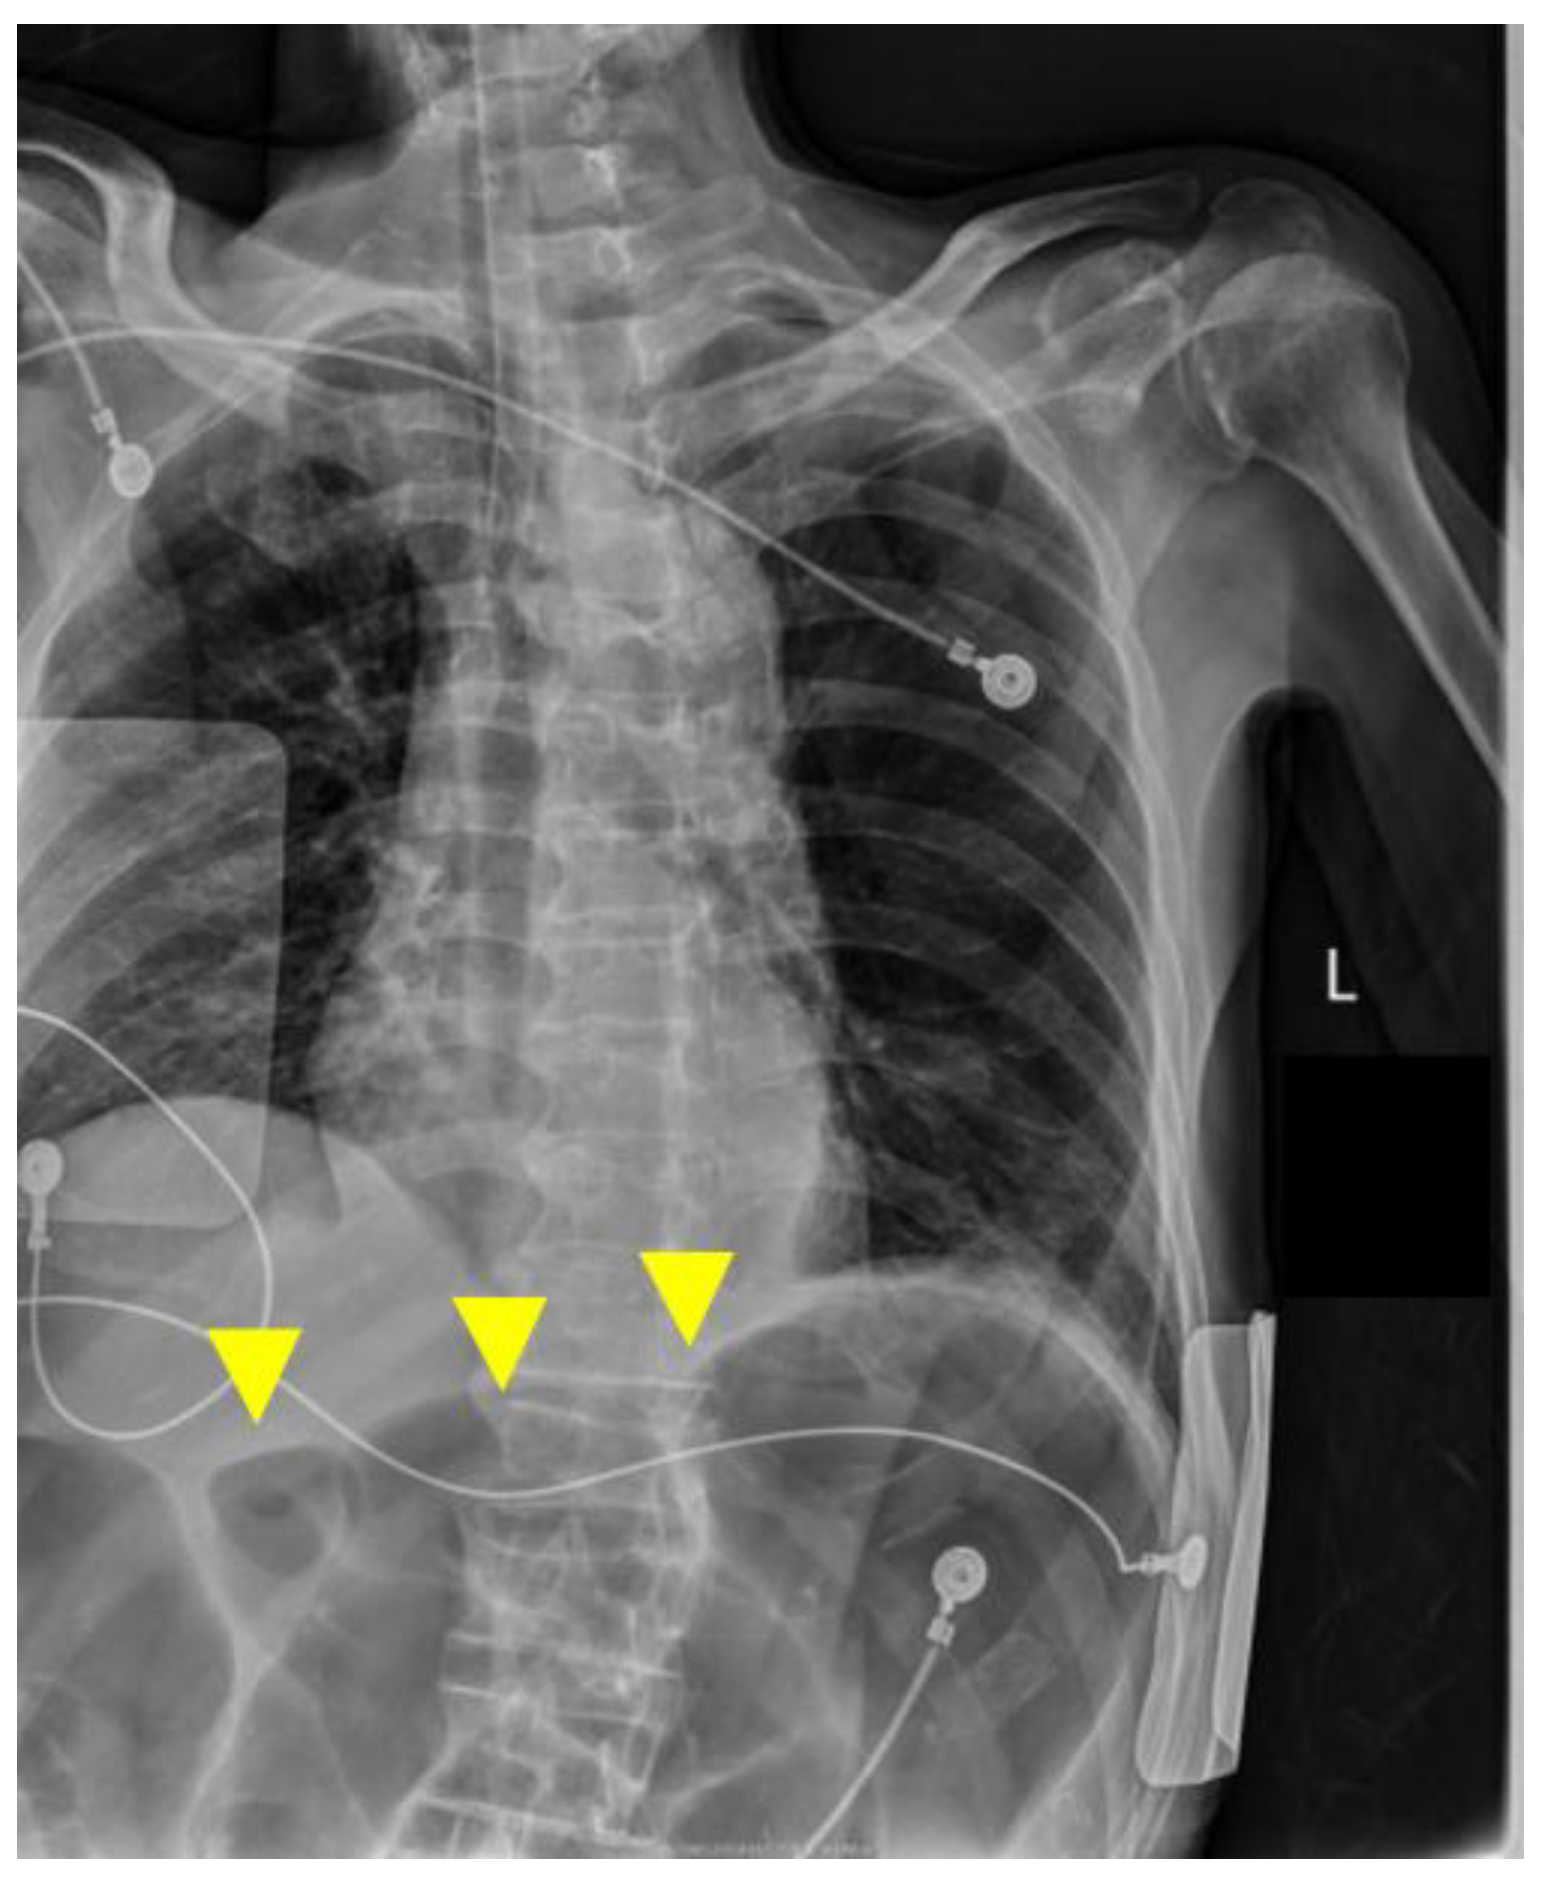

Chest CT showed mild bronchopneumonia predominantly in the right lower lobe without extensive consolidation or large pleural effusions (Figure 1A). On the same CT series, a moderately distended transverse colon with intraluminal gas was incidentally visualized within the scan range, suggesting pre-existing colonic dilatation at admission (Figure 1B). Non-contrast head CT confirmed bilateral CSDHs, more prominent on the right, compressing both cerebral hemispheres (Figure 2A).

Figure 1.

Initial computed tomography (CT) on admission. (A) Chest CT demonstrating mild bronchopneumonia predominantly in the right lower lobe without extensive consolidation or pleural effusion (yellow circle). (B) The same CT series incidentally showing a moderately distended transverse colon with intraluminal gas (yellow arrowhead). This finding was visible on the admission CT but was not pursued with dedicated abdominal evaluation at that time and was later revisited during case review.